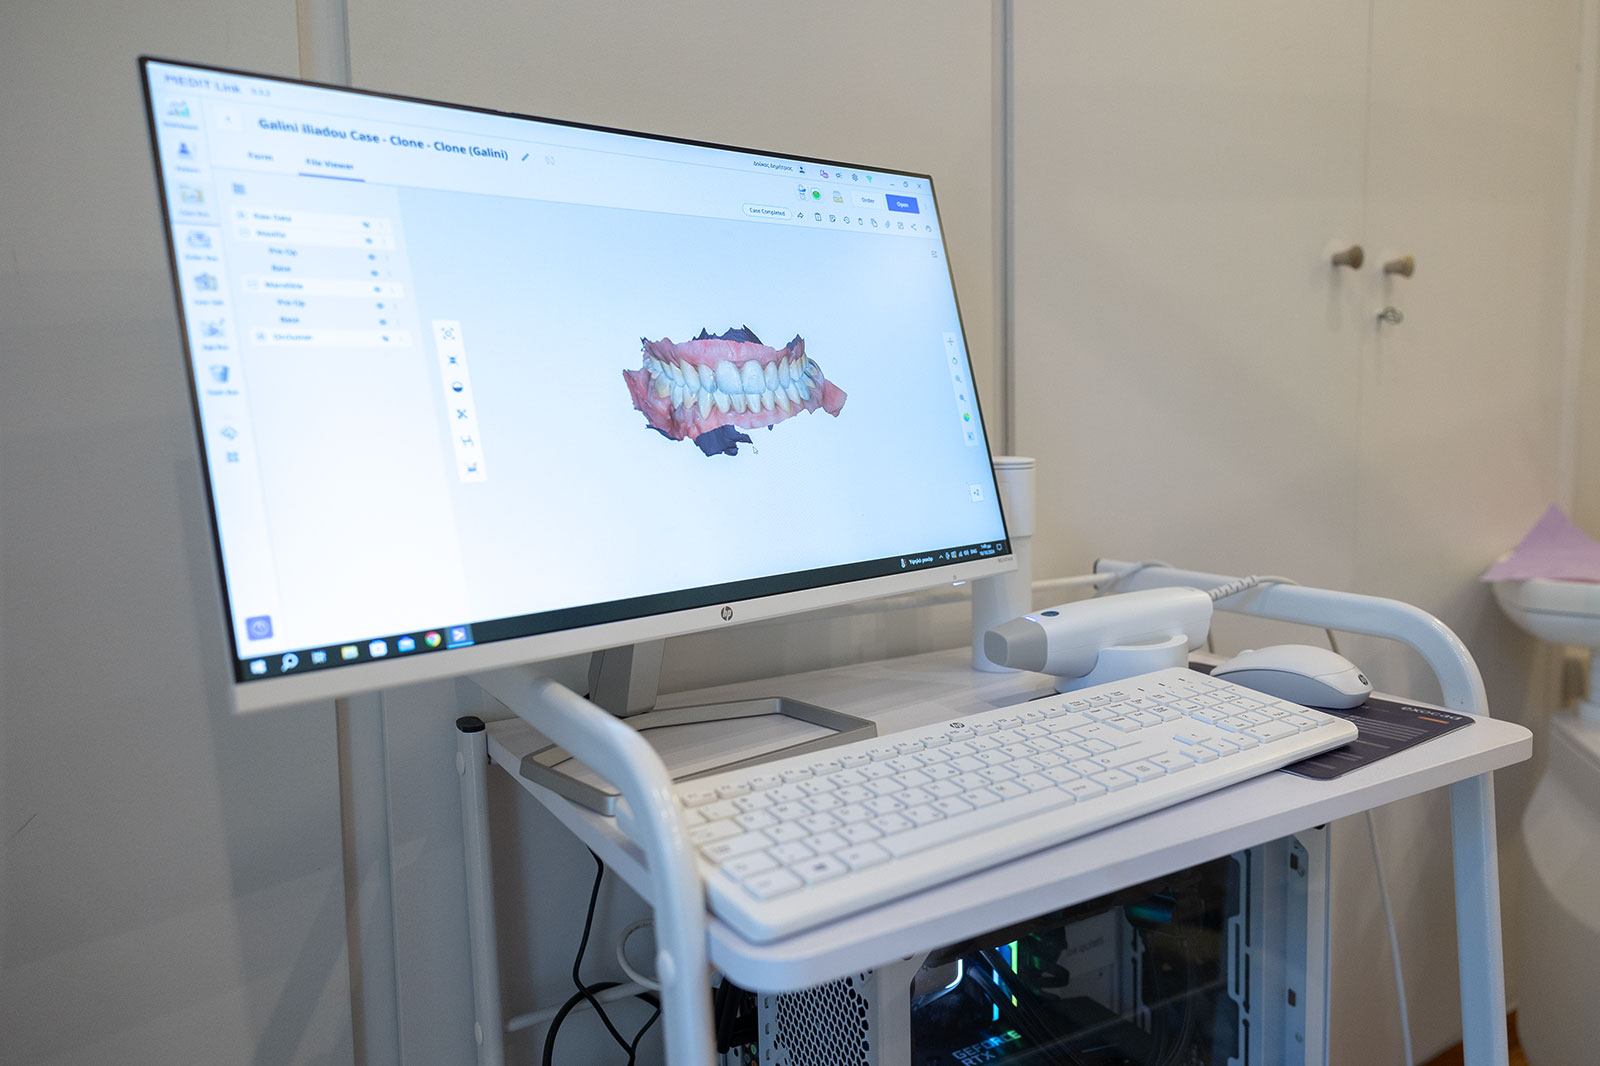

Intra Oral Scanner

Ολες μετρήσεις για την κατασκευή των προσθετικών αποκαταστάσεων, σε φυσικά δόντια, σε εμφυτεύματα αλλά και σε περιπτώσεις που χρειάζεται κινητή προσθετικη εργασια, γίνονται ψηφιακά με ενδοστοματικο σαρωτή.

Με αυτόν τον τρόπο επιτυγχάνεται μεγαλύτερη ακρίβεια στην εφαρμογή των προσθετικών αποκαταστάεων, λιγότερη δυσανεξία στις οδοντιατρικές σιλικόνες που χρησιμοποιούνται με τον παραδοσιακό τρόπο καταγραφών και μείωση του αριθμού των επισκέψεων.